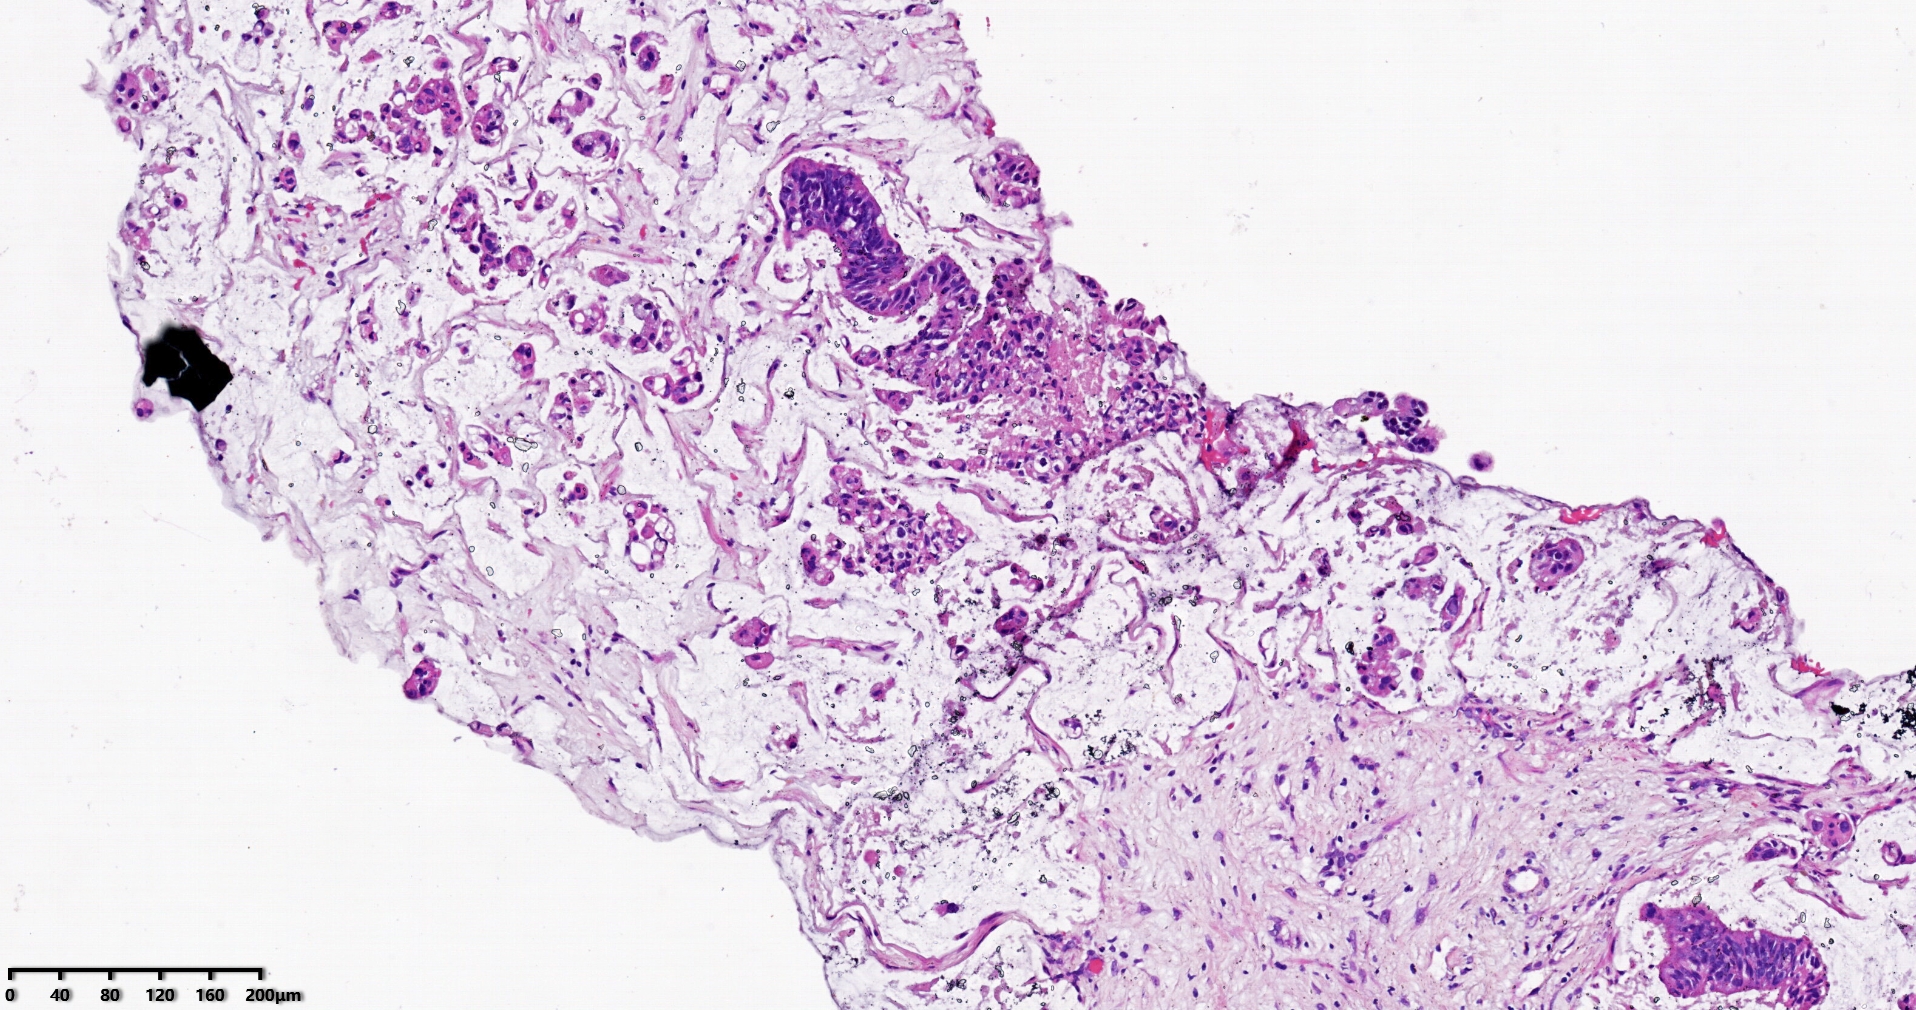

标本名称肝脏穿刺

大体所见灰白灰红色穿刺活检组织两条,长1.7-1.9cm,直径0.1-0.2cm。

考虑符合:肝内胆管癌

考虑转移性黏液腺癌,消化道来源可能,建议做免疫组化,排除胆管源性。